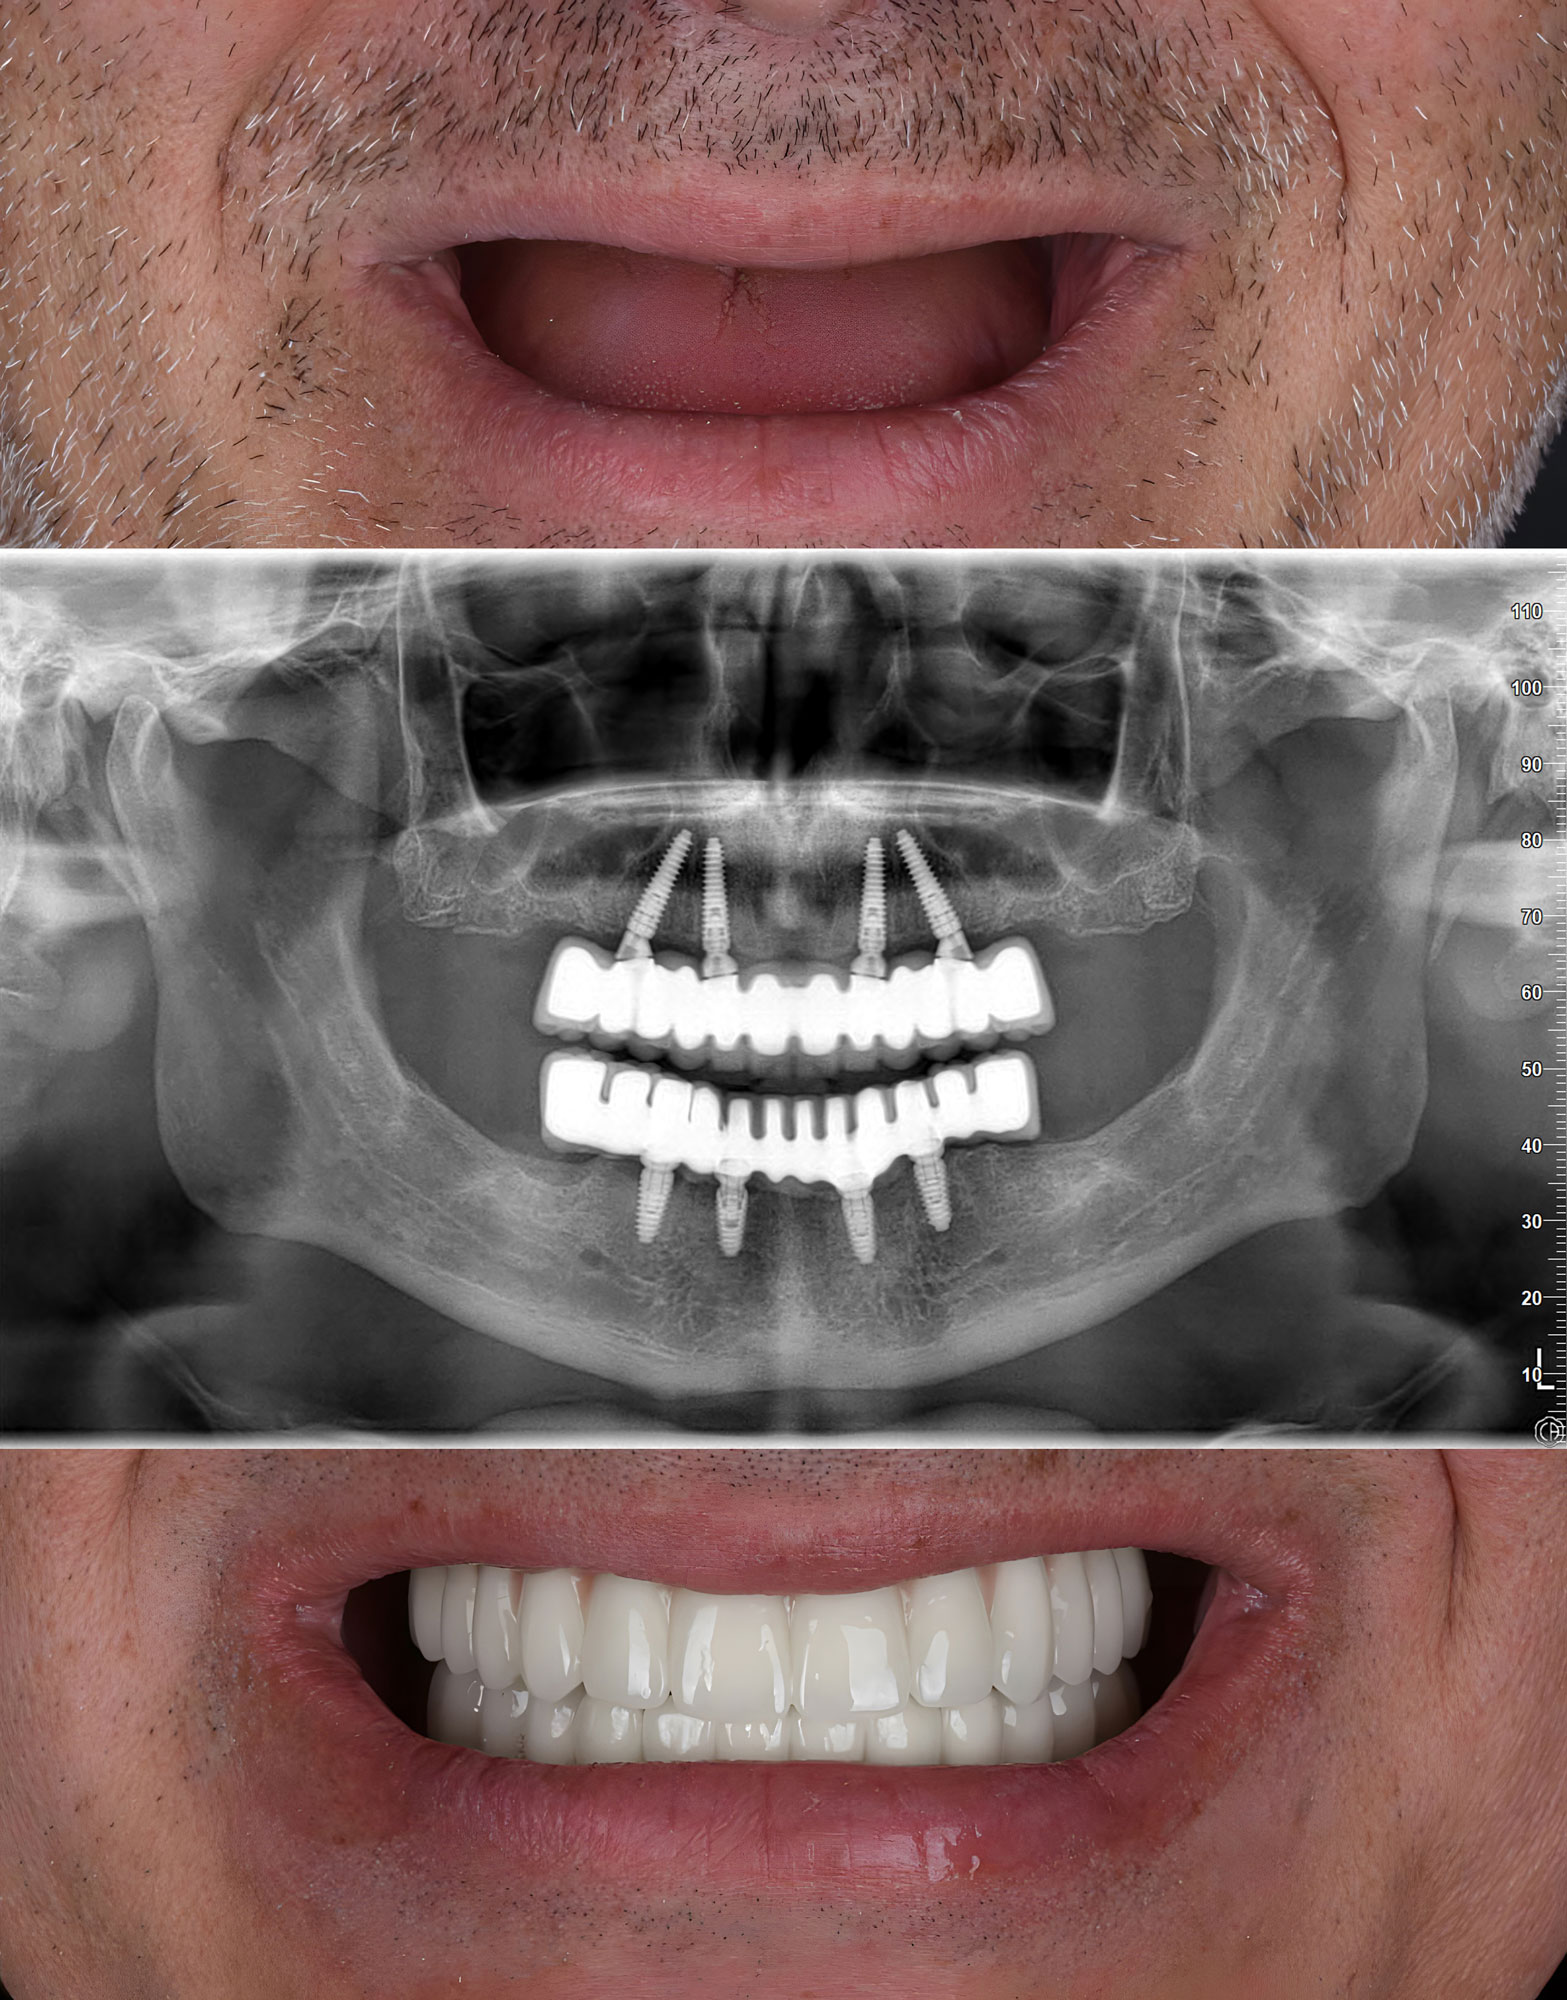

How All-on-4 Differs From Traditional Dental Implants

All-on-4 offers a streamlined alternative to traditional implant treatments. It’s designed specifically for patients who need a full arch of teeth but want to avoid the time and cost of placing multiple individual implants.

- Fewer implants required: Just four strategically placed posts can support an entire arch

- Faster timelines: Many patients receive a functional set of teeth the same day

- Bone-saving approach: Angled implants reduce the need for bone grafting in many cases